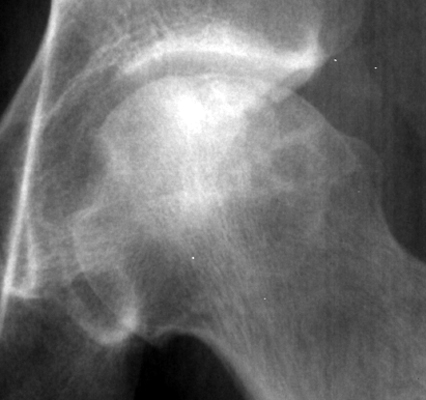

A radiograph of a left hip joint, which reveal a thin, curvilinear lucent line parallel to the cortical margin of the femoral head. Interruption of the blood supply to the femoral head leads to ischemic necrosis of the marrow and bone that it supplies. Eventually, the bone infarcts and insufficiency fractures may ensue. Fractures that occur in the subchondral bone may be recognized by a crescentic lucent zone that separates the fragment from the remainder of the femur.

AP hip - Click on the image for a larger version